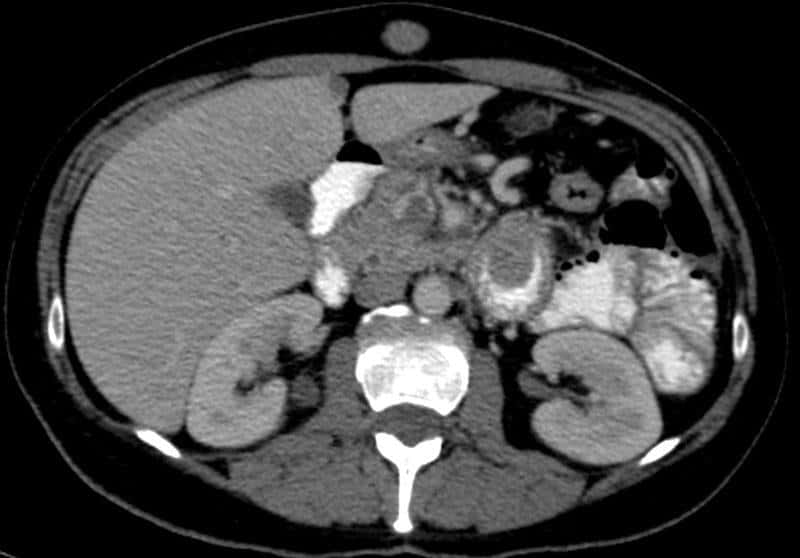

Di căn ruột non

» Thông tin: Nữ giới – 56 tuổi.

» Lâm sàng: Đau bụng.